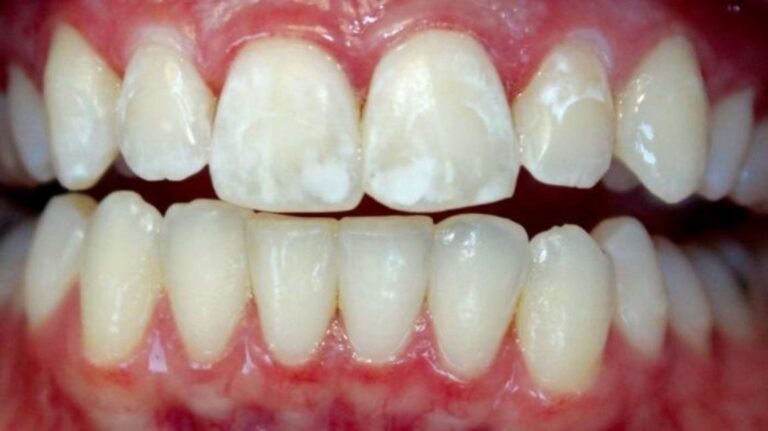

ЛЕЧЕНИЕ КАРИЕСА у детей

ПРОФИЛАКТИКА ЗАБОЛЕВАНИЙ